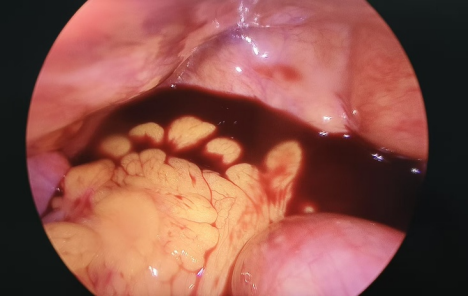

湖南省中西医结合医院(湖南省中医药研究院附属医院)妇科团队随即为其安排急诊腹腔镜手术,术中见盆腔内出血约300ml。术后经过精心护理,已安全出院回家。追溯病因,正是此次排便时过度用力导致腹压骤增,成为黄体破裂的直接诱因。

下图为术中所见: